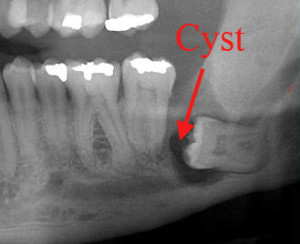

Cysts and Tumors: In rare cases, the tissue surrounding the impacted wisdom tooth can become infected, increasing the risk of a cyst or tumor development.